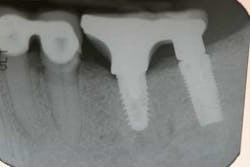

Case study A 58-year-old male with a noncontributory medical history presented to a private practice for a complete rehabilitation of his dentition due to years of bruxism and parafunction. (Fig. 1) After surgical and restorative consultations, a treatment plan was fabricated. The treatment plan included restoring his lost vertical dimension, restoring his natural dentition with porcelain-fused-to-metal full-coverage crowns, and replacing his lost posterior teeth with dental implants. After his vertical dimension was restored with an acrylic bite plate to a position harmonious with TMJ function, crown-lengthening surgery was performed. (Fig. 2)Fig. 2 Six weeks after, the teeth were temporized to develop soft tissue margins/interdental papillae. (Figs. 3 and 3a) The patient was kept in temporaries for three months, during which time an implant was placed in site No. 19. Both the natural dentition and the implant were completed at the same time, three months after implant placement. (Fig. 4) Because of the patient’s occlusal issues, the implant was screw-retained, and the patient was given a maxillary night guard. Three weeks after insertion, the patient presented with a loose abutment screw. The dentist tightened the screw and sent the patient home. This cycle was repeated two more times until the patient presented again with a loose crown, but this time, a fracture implant screw. The dentist attempted to remove the screw with a Cavitron and drilling the implant screw out to release preload, but to no avail. The case was then referred to my office for implant removal.